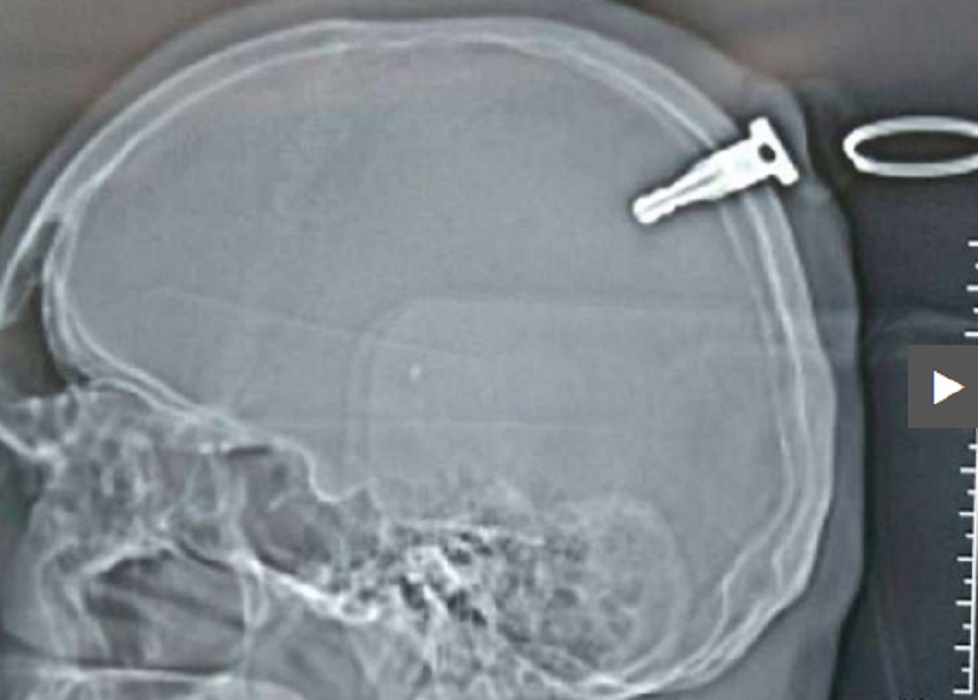

GHODEGAON – Un 19enne originario dello Stato indiano del Maharashtra è stato sottoposto ad un delicatissimo intervento chirurgico dopo che gli è finita conficcata in testa una chiave da moto, che se si fosse posizionata pochi centimetri più in là lo avrebbe ucciso.

Il giovane ha subìto il terribile infortunio durante una rissa nel villaggio di Ghodegaon nel distretto di Ahmednagar. È stato dimesso tre giorni dopo l’incidente e pare si stia riprendendo.

“Questa settimana è previsto un controllo di routine, ma le sue condizioni fanno ben sperare”. Le immagini rilanciate da Dagospia sono molto forti e mostrano chiaramente le chiavi conficcate nel cranio.